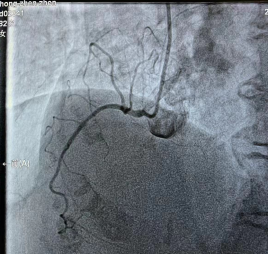

2023-10-19_勇攀“心”高峰——记商城县人民医院心血管内科介入能力再突破!_8.jpg

回旋支未见明显狭窄,远端可见慢血流